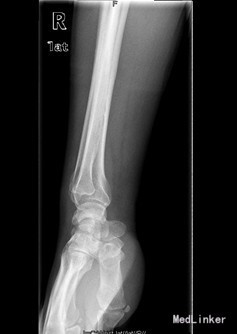

患者男,60岁,因“右腕部疼痛5月,右小指屈曲障碍20天”入院。入院前5月,患者无明显诱因情况下出现右侧腕部尺侧酸痛不适,未就诊治疗。左小指伸曲正常;入院前20天,患者出现右小指屈曲障碍,无小指指麻木,遂来我院治疗,门诊以“左小指深浅屈肌腱迟发性断裂”收入院。

查体:右侧小指伸直位,不能屈曲。右侧腕部尺侧可触及一质韧包块。右小指感觉正常,末梢循环正常。右小指不能主动屈曲掌指关节及中节、末节手指;伸指正常,余手指活动正常。 辅查:彩超:右腕包块处肌腱周围粘稠积液伴滑膜增厚。

初步诊断:右小指深浅屈指肌腱迟发性断裂 诊疗计划:择期行右手小指屈指深肌腱探查修复术

术中发现右手小指深浅屈肌腱陈旧性断裂、瘢痕形成,有粘连,邻近滑膜增生变性,右手小指、环指及中指屈指肌腱变性毛糙,有较多淡黄色积液。